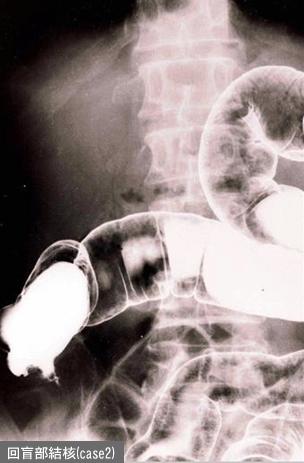

Comparative diagnosis of inflammatory disease at the boundary region of the digestive tract.

Tokyo Pref., Centro Nacional de curaciones de Cáncer, Hospital Central y Centro Kyusyu de Curaciones de Cáncerc

colon/ileocecal

Rayos X